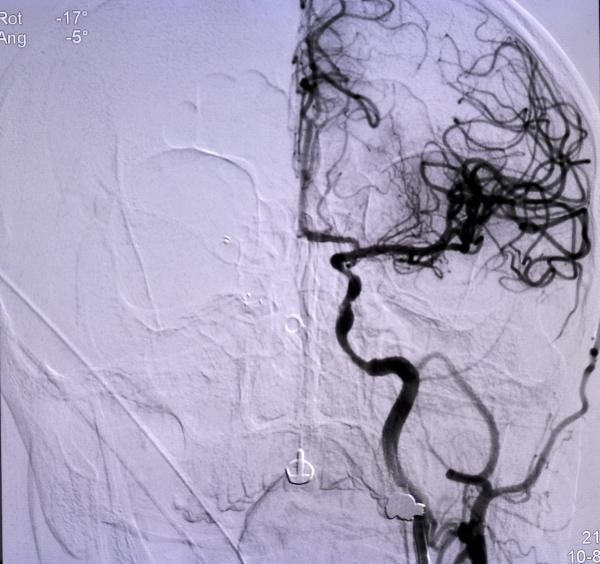

Niğde’den ellerinde uyuşma şikayeti sonrası başvurduğu hastaneden Konya’ya sevk edilen Ömer Altan’ın (73), kısa sürede müdahalesi yapılarak, tıkanan ana damarını açtıklarını belirten Doç. Dr. Gökhan Özdemir, “Hastamız Niğde şehrinden bize başvurdu. Oradaki hekim arkadaş hastayı değerlendirdi. Beyni besleyen ana büyük damarında ciddi bir darlığı tespit etti. Bu da hastanın felç geçirmesine sebep olan bir durum. Oradaki doktor arkadaş hızlıca bize ulaştı ve biz de hastayı kabul ettik. Bekletmeden burada hastanın müdahalesini yaptık, ana damarını açtık. Ana damar olduğundan dolayı bu hastaların büyük bir kısmı ölüyor. Yani beyni besleyen ana büyük damarlardan biri tıkandığı zaman genelde bu hastanın yüzde 50-60’ı ölüyor. Ölmese bile büyük ihtimalle ömür boyu özürlü kalacaktı” dedi. (DHA)